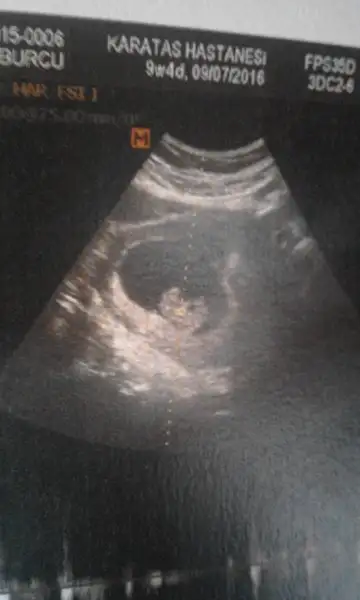

ilki 6 haftalık diğer ıkısı 9 hafta 4 gün karından sizce nedir

Eklentiler

• 20151210_105137.webp

20151210_105137.webp

9,6 KB · Görüntüleme: 489

• 20151205_095328.webp

20151205_095328.webp

12,4 KB · Görüntüleme: 436

• 20151210_105120.webp

20151210_105120.webp

16,4 KB · Görüntüleme: 501